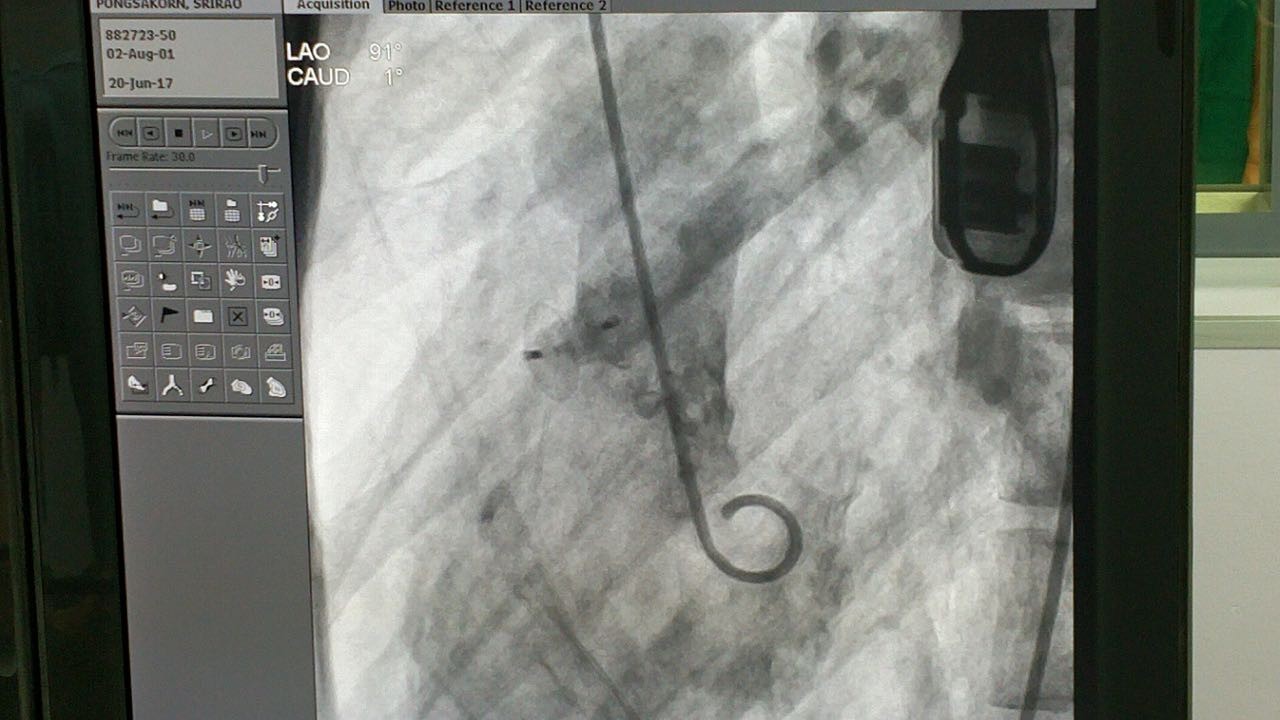

第四台手术

第四例手术患者经诊断为膜周部室间隔缺损并伴有室缺瘤。术中测量患者瘤体直径为12.5mm,左室入口为9.92mm,右室出口为3.27mm,且其室间隔缺损位置较为特殊,位于主动脉瓣正后方并非常靠近三尖瓣。病人同时具有三尖瓣反流的症状。本例手术的主要术者Dr.Pimpak Prachasilchai选用彩神在线网信彩票-彩神通免费版下载-彩神8争霸vlll-彩神购彩购彩大厅-彩神软件陆立根免费版-彩神ll争霸3-彩神ll彩神8-彩神ll争霸彩票-拼搏在线彩神网网页版科技公司型号为LT-MFO-8-6的KONAR-MF™多功能封堵器,通过主动脉路径释放成功。病人缺损部位封堵完全,无残余分流,三尖瓣未受干扰。

(术中造影)

(Dr.Pimpak Prachasilchai使用KONAR-MF™多功能封堵器进行封堵手术)

(术后造影)